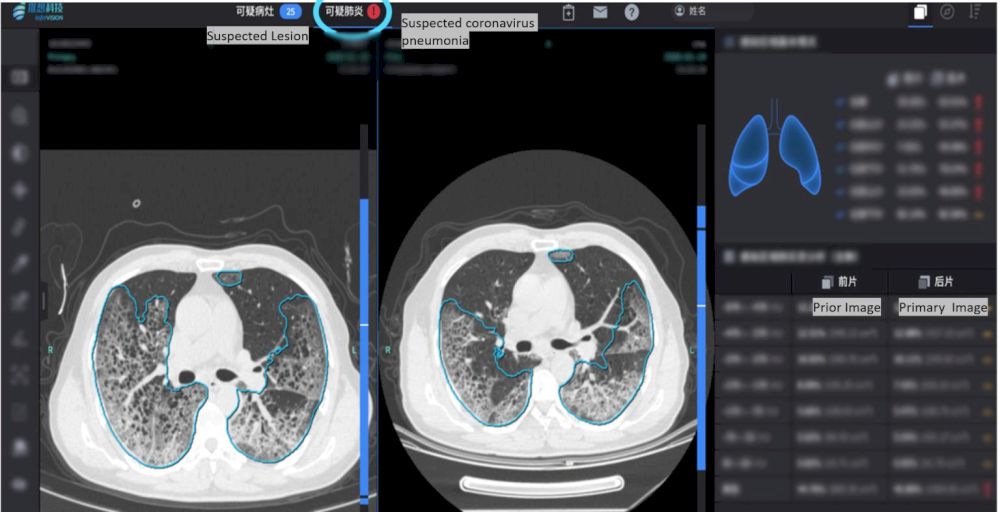

继加拿大疾病专家警报机构蓝点Bluedot的AI算法率先发出新型冠状病毒(Covid 19)预警之后,由北京初创公司推想科技(Infervision)开发的AI软件正在武汉帮助医生更快的进行诊断。

据悉这款新冠病毒辅助筛查和疫情监测系统是该公司和华中科技大学同济医学院附属同济医院、武汉大学中南医院、深圳市第三人民医院联合研发,并于2月20日在世界权威医学杂志《柳叶刀》系列文章中受到关注

目前Infervision这套AI软件已经在中国超过34家医院部署,目前正在美国和欧洲市场进行评估。到目前为止,它已经帮助审查了32,000多个Covid 19潜在案例。基于AI的软件的主要优势在于,由于有症状的患者滞留在医院中,因此其快速诊断可以帮助快速对患者进行分类。该软件还可以很好地用于交叉比较和在多次检查中分析肺部发育。